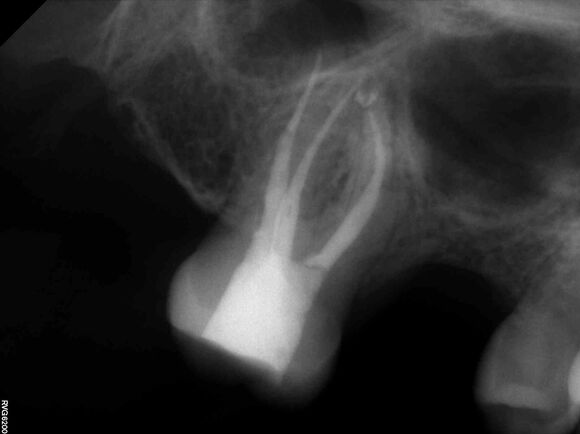

Beispiel 1: Vorher

Schwierige Krümmungen und sehr grazile Wurzeln.

Beispiel 1: Nachher

Die perfekte Wurzelfüllung!